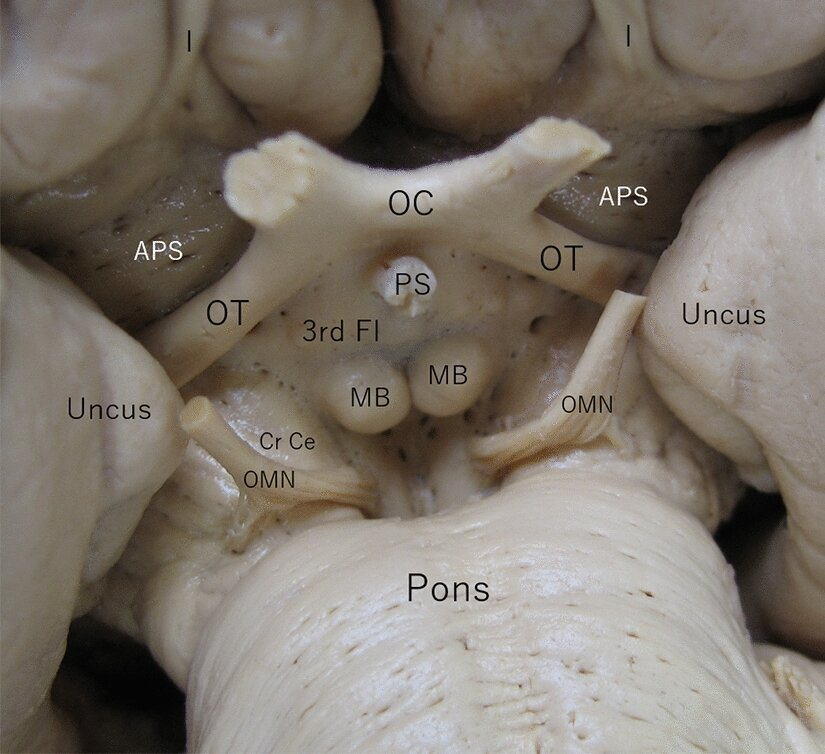

Where can we find mamillary bodies

posterior to optic chiasm

Piriform cortex is made up of:

Entorhinal cortex = landmark of hippocampus

Uncus = landmark of amygdala

amygdala and hippocampus are above these structures